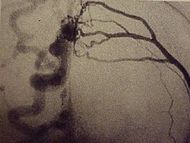

Диагноз ставится после осмотра врачом и проведения ряда дополнительных методов исследования. С помощью стетоскопа, приставленного к месту фистулы, слышен машинный шум. Окончательно диагноз подтверждается после проведения ультразвукового дуплексного сканирования ( сочетание допплеровского ультразвукового сканирования с традиционным ультразвуковым исследованием), ангиографии или МР-ангиографии.

Медицинские процедуры, проводимые при заболевании артериовенозная фистула: Ультразвуковое дуплексное сканирование, Ангиография, Магнитно-резонансная ангиография